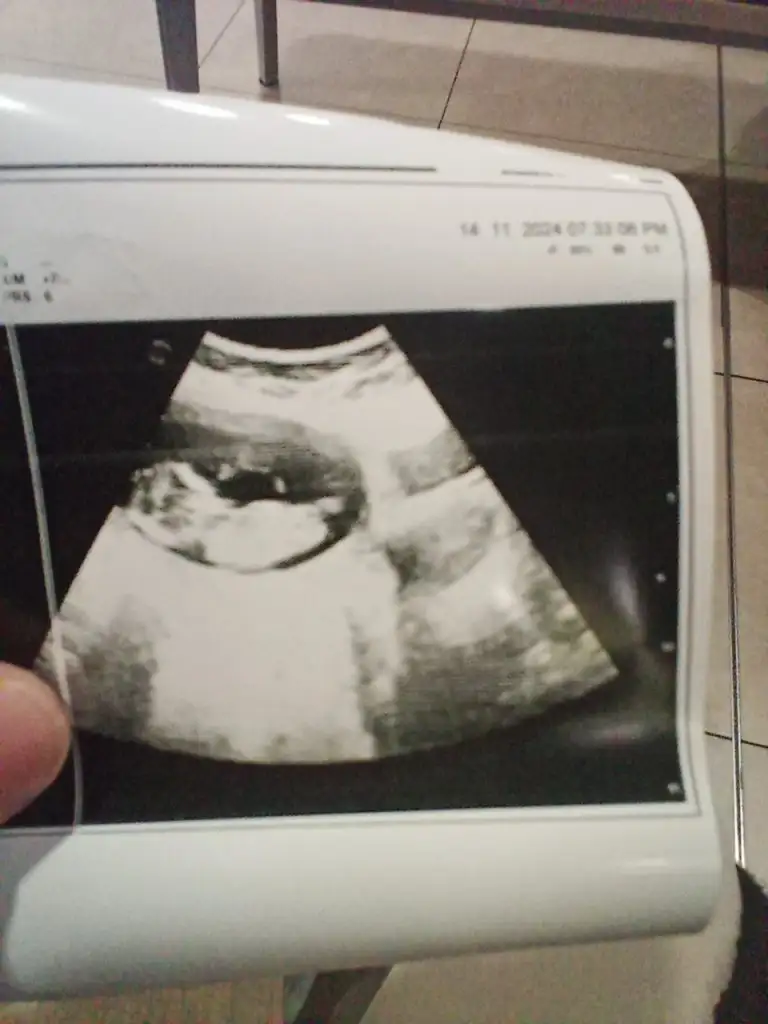

Bizde yorum alabilirmiyiz

İyi akşamlar kızlar bizde bügün kontrole gittik 6+3 ama kalp atışını çok net duyamadık böyle belli belirsiz gibi doktor korkmayın var kalp atışı erken olduğu için net değil dedi o nasıl oluyorsa anlayamadım

Merhaba evet benziyor gibi ama ben pek anlamıyorum kaç haftaliksiniz bende dr söyleyince öğrendim gönlünüzden gecenin nasip olmasını dilerim